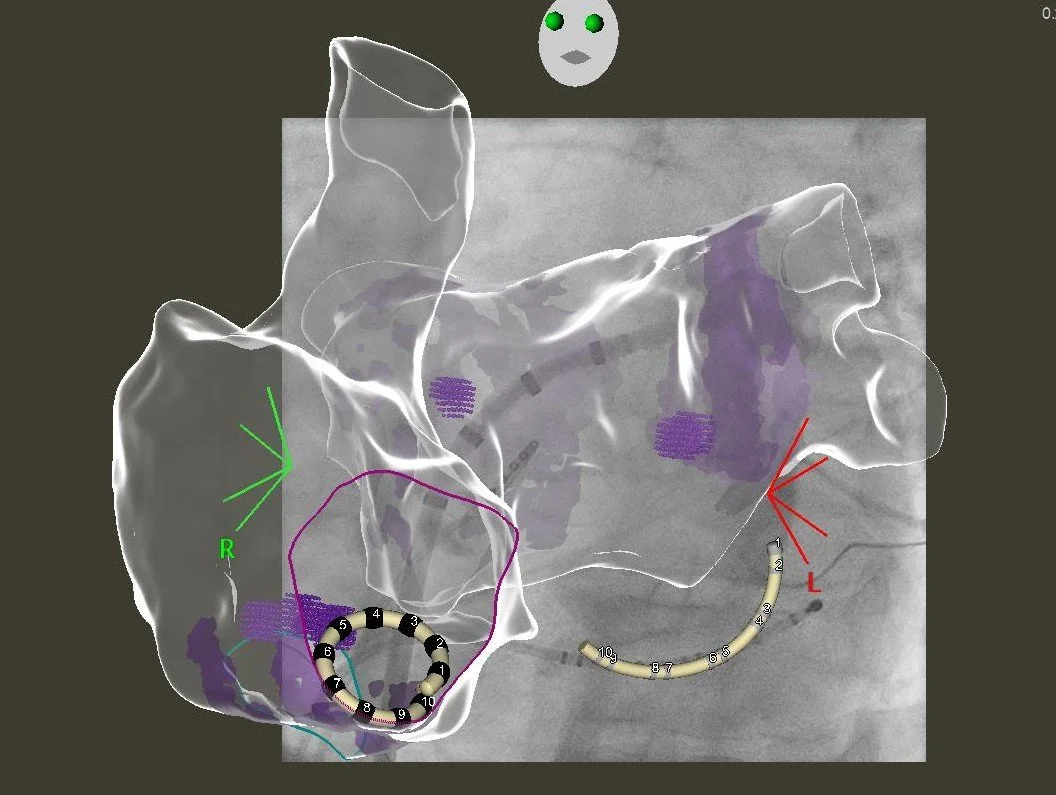

Als Radiofrequenzablation wird die gezielte Behandlung von Gewebe mit Hitze bezeichnet. Vorangeht die Erstellung einer “elektrischen Landkarte” Ihres Herzens unter Verwendung eines 3D-Navigations-Systems. Aufgrund moderner Röntgen-Integration können die Eingriffe weitgehend strahlenfrei, in speziellen Fällen - etwa bei schwangeren oder stillenden Patientinnen - auch gänzlich strahlenfrei erfolgen.

Anhand der elektrischen Landkarte kann die Therapie ganz individualisiert geplant und zielgerichtet und schonend durchgeführt werden. Im Gegensatz zur PFA Technologie können hier auch Therapieziele außerhalb der Lungenvenen in gleicher Sitzung behandelt werden.

Ein dreidimensionales medizinisches Modell des Herzens mit farbiger Oberflächenanzeige auf einem Röntgenbild. 3D Navigation einer Vorhofflimmerablation

Ultra-hochauflösende Mapping-Verfahren

Besondere Fälle bedürfen besonderer Ansätze - wir verwenden modernste, hochauflösende Mapping-Katheter um das genauste Bild aus ihrem Herzen zu erhalten. Hierbei kommen zunehmend auch KI-gestützte Algorithmen zur Datenaufarbeitung zum Einsatz. Die so erstellten extrem detaillierten elektrischen Landkarten helfen dabei, die zugrunde liegende elektrische Erkrankung besser zu verstehen und gezielter zu behandeln - die Verödung wird damit effizienter und erfolgreicher